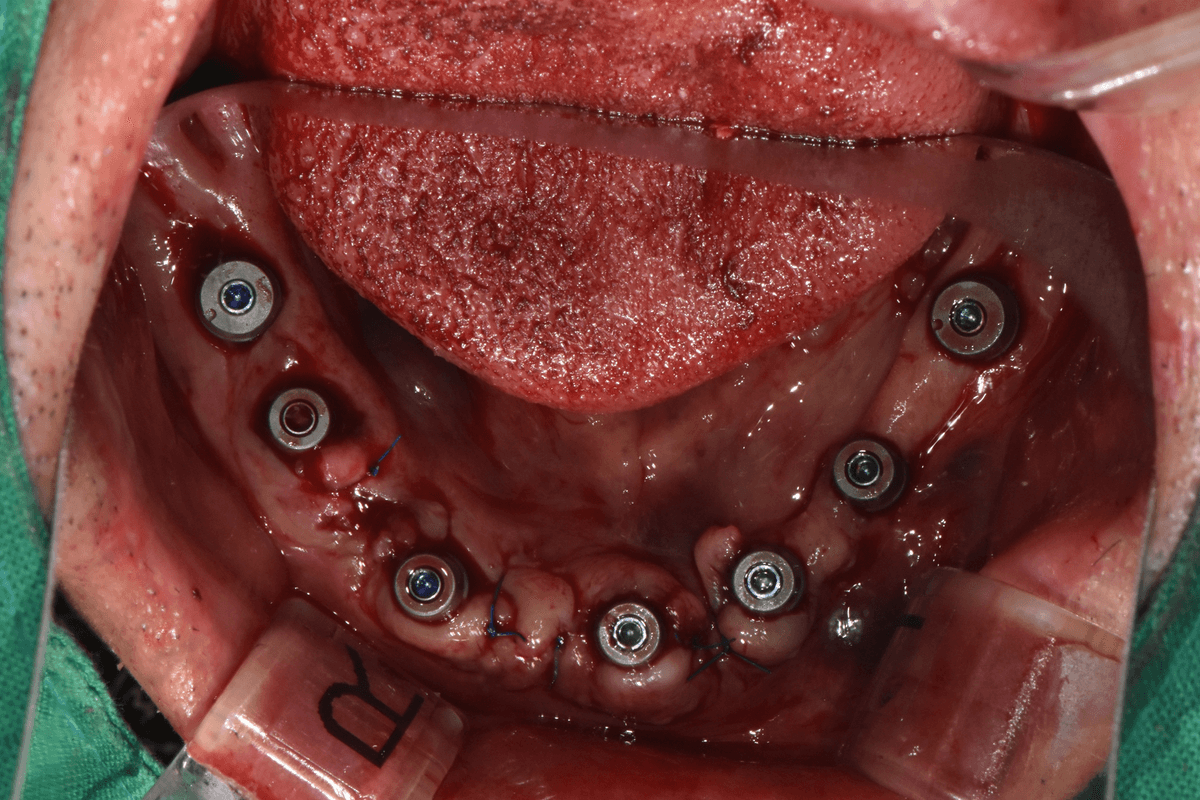

복잡한 케이스 대응

대학병원급 경험으로 악교정, 매복치 교정 등 난이도 높은 케이스 대응

교정 치료 전후 사례

교정과 전문의가 직접 진료한

실제 환자 케이스입니다

이●● · 심한 부정교합